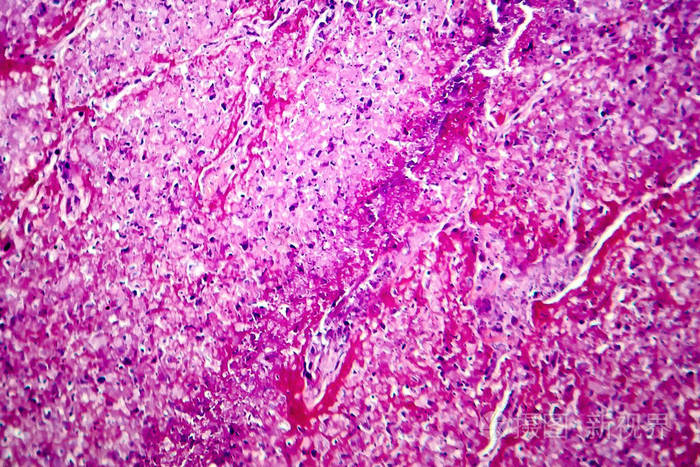

肺结核肉芽肿干酪化光镜观察

肺结核非坏死性肉芽肿